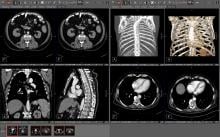

Optimizing radiology workflow begins well before a radiologist opens an exam. Early planning and preparation are critical to driving efficiencies and prioritizing patient care. However, in many practices today, radiologists still spend time looking for pertinent patient information, digging through past reports, and searching for relevant priors before they can read an exam.

On the workflow side, several vendors are leveraging AI to pull together all of a patients' information, prior exams and reports in one location and to digest the information so it is easier for the radiologist to consume. Often the AI pulls only data and priors that relate to a specific question being asked, based on the imaging protocol used for the exam. One example of this is the Siemens Healthineers AI Clinical Pathway and Siemens AI integrations with PACS to automate measurements and advanced visualization.